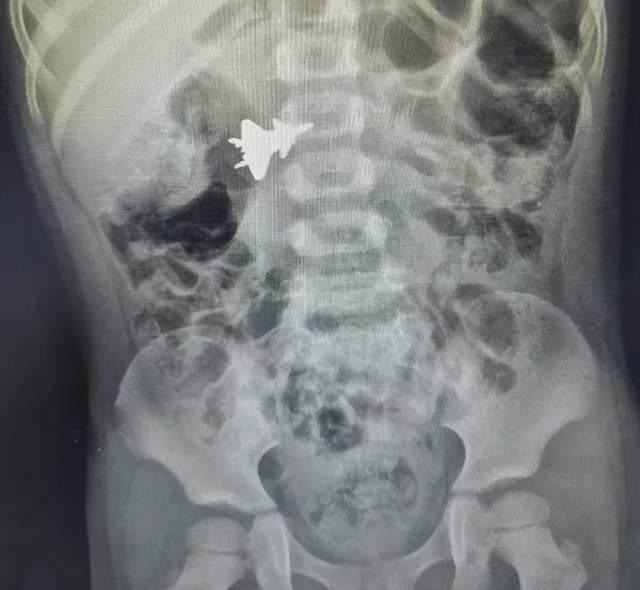

其实这张图片的来源来自于一张医院的X光检测图。

2023年6月份的时候,南宁4岁的男孩小明(化名)误吞了金属的玩具飞机。之后小孩的家人紧急将孩子送往医院,拍摄了一组X光检测图。

这个小男孩吞掉的金属玩具飞机,就是以歼-20为原型生产出来的。于是在X光的照射下,这个金属玩具就形成了“歼-20战机在小孩腹腔中飞行”的效果。

再然后这些X光照片不知道怎么的传播到了互联网上,于是一些不知道从哪冒出来的人拿着这些X光照片裁剪一番,将明显的人体骨骼、腹腔图案裁剪掉,只留下了模糊的“歼-20”的图案,形成了“真正的歼-20战机被拍摄下明显照片”的效果。

最后这帮人拿着裁剪过的照片,开始宣称这是“日本F-35战机EOTS锁定歼-20”的证据。